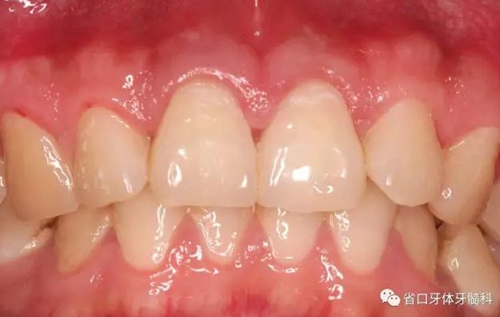

圖1:術前口內(nèi)照

檢查:11、21牙體組織完整,冷熱刺激無明顯疼痛不適,叩診+,松-,牙齦無紅腫,探診深度2-3mm,電活力測試同正常對照牙,數(shù)值為5,正常對照牙為4;